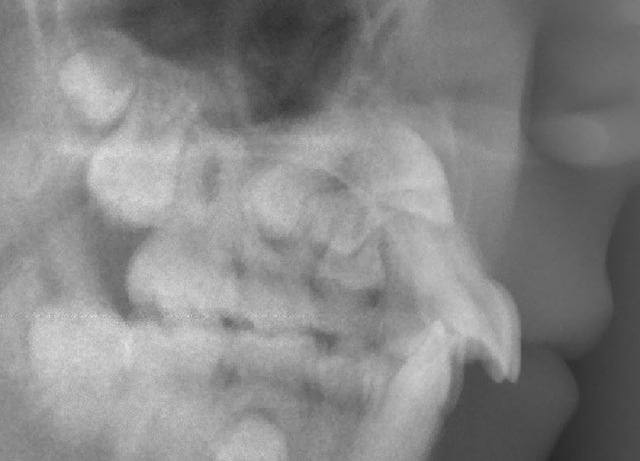

Jeune fille de 12 ans.

Que proposez-vous ?

Comment procéderiez-vous ?

Il n'y a aucun élément caché, cette panoramique se suffisait à elle-même pour montrer toute la problématique du cas en trois points :

- 13 incluse.

- 23 incluse.

- 14 "un peu" penchée, sa racine passe au dessus de l'apex de la 53 et vient titiller la couronne de la 13.

À votre avis, au vu de la téléradio de profil, 13 et 23 sont-elles incluses en vestibulaire ou en palatin ?